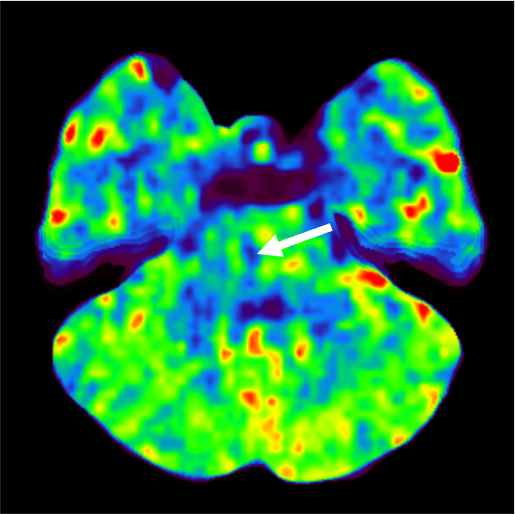

発症5日目に脳血管評価目的でCT angiographyの撮像依頼あり。MRI撮像ができないため、脳梗塞評価も兼ねて、全脳の多時相CT angiographyを撮像し、同一の収集データからCT perfusion画像も評価した。TIAの臨床診断であったが、単純CTとCT perfusionの所見から急性期~亜急性期ラクナ梗塞と診断した。

当該疾患の診断における造影CTの役割

急性期脳梗塞に対する血栓回収療法の適応判断においてCT perfusionの有用性が報告されている1-3)。CT perfusionは迅速にTmaxやCBFなどからischemic coreやpenumbraの評価が可能であり、また自動解析ソフトを用いることで客観的な定量評価が可能となる。320列CTで撮像すると、同じ撮影データから最適なCT angiographyやCT venography、多時相CT angiographyが再構成可能であり、脳梗塞の機序評価や血栓回収療法の治療戦略決定において有用である。本症例のようにMRI禁忌患者においては特にCT angiographyやCT perfusionが有用であった。